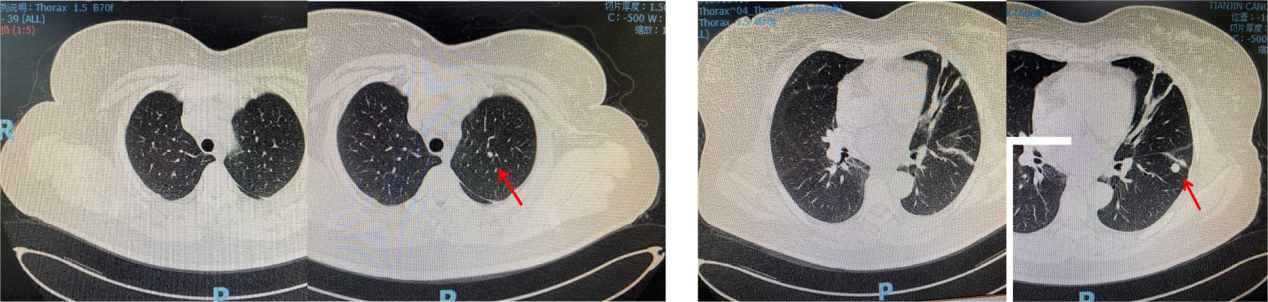

疾病进展:2020年6月,颈、胸部CT显示,双肺多发结节,考虑转移;上腹部强化MRI显示未见明显变化。

疾病进展:2021年1月,颈、胸部CT显示,双肺部分结节较前略增大。基因检测:伴PIK3CA突变。

疾病进展:2021年7月,颈、胸部CT显示,双肺多发结节较前略增大。

2022年7月复查疾病进展,双肺出现新发病灶。